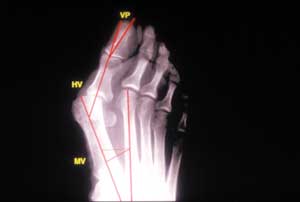

Technique Technique de l'ostéotomie de la 1ère phalange du gros orteil dite en "sandwich" dans la cure chirurgicale de l'hallux valgus , C. Camelot Service de Chirurgie Orthopédique, Traumatique et Réparatrice Hôpital de la Pitié - 83 bd de l'Hôpital - 75013 Paris , J.-F. Lelièvre Service de Chirurgie Orthopédique, Traumatique et Réparatrice Hôpital de la Pitié - 83 bd de l'Hôpital - 75013 Paris , S. Ramaré Service de Chirurgie Orthopédique, Traumatique et Réparatrice Hôpital de la Pitié - 83 bd de l'Hôpital - 75013 Paris , Gérard Saillant CHU Pitié-Salpêtrière, Paris, France N°104 - Mai 2001 ● 15 min de lecture